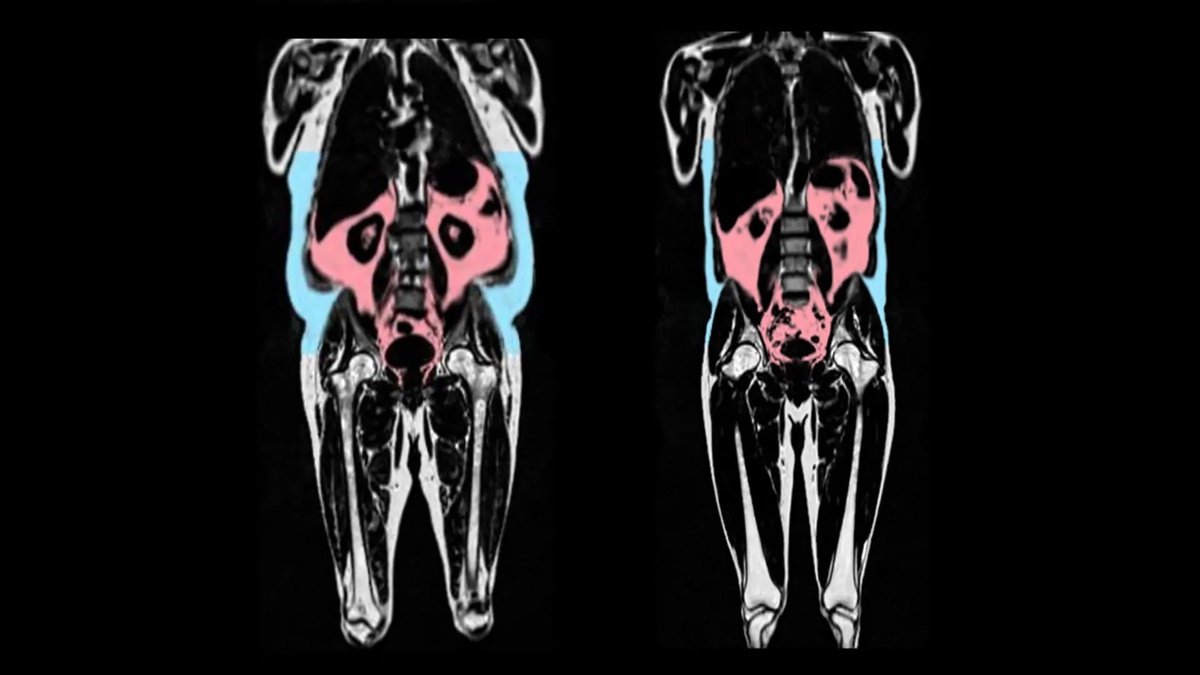

Скрытый жир ускоряет старение сердца Исследование показало, что избыток висцерального жира, окружающего внутренние органы, связан с ускоренным старением сердца. Висцеральный жир трудно заметить, так как он находится глубоко в брюшной полости вокруг органов, таких как желудок и печень. Он может вызывать воспаление, что способствует преждевременному старению. У мужчин, имеющих больше жира вокруг живота, сердце стареет быстрее. У женщин жир на бедрах и ягодицах может замедлять этот процесс. Также у женщин более высокие уровни эстрогена могут защищать сердце от старения. Это открытие может помочь в разработке новых методов лечения, направленных на замедление старения сердца.

Исследование показало, что избыток висцерального жира, окружающего внутренние органы, связан с ускоренным старением сердца. Висцеральный жир трудно заметить, так как он находится глубоко в брюшной полости вокруг органов, таких как желудок и печень. Он может вызывать воспаление, что способствует преждевременному старению. У мужчин, имеющих больше жира вокруг живота, сердце стареет быстрее. У женщин жир на бедрах и ягодицах может замедлять этот процесс. Также у женщин более высокие уровни эстрогена могут защищать сердце от старения. Это открытие может помочь в разработке новых методов лечения, направленных на замедление старения сердца.